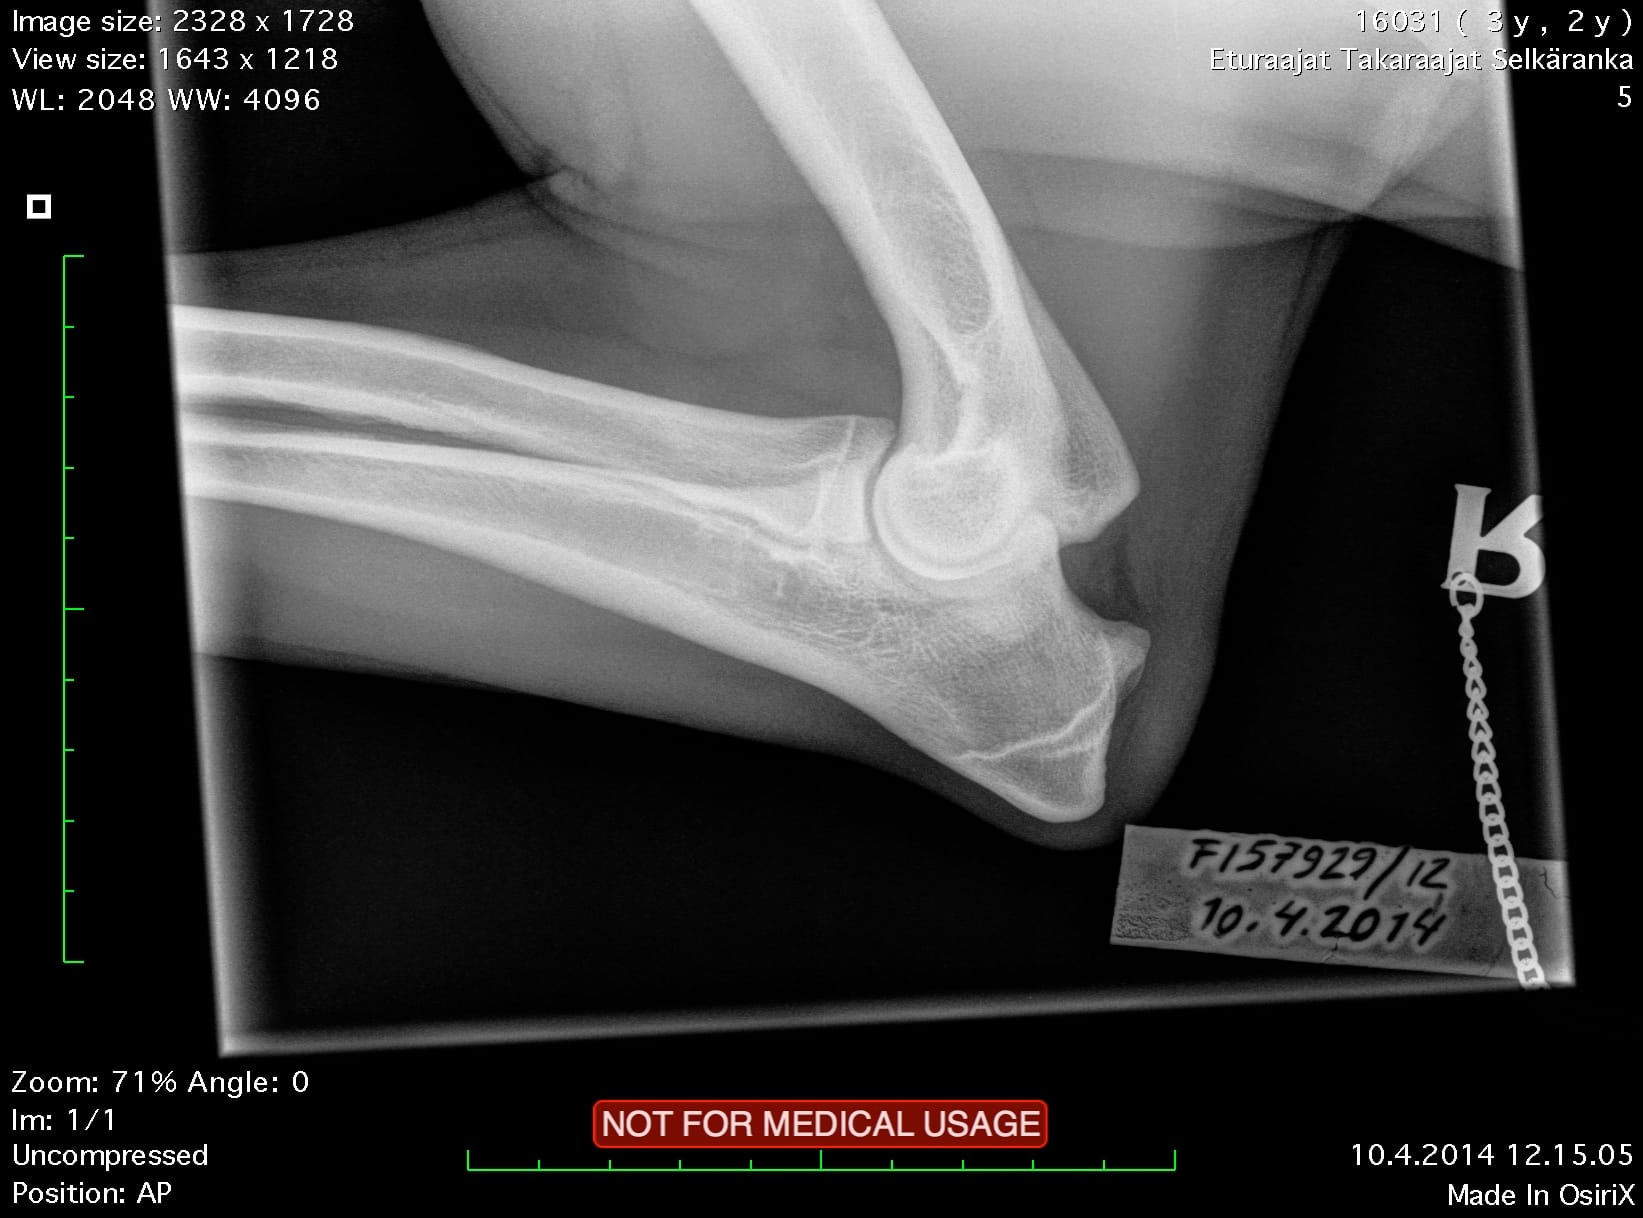

Oiva Kyynärnivel LAT